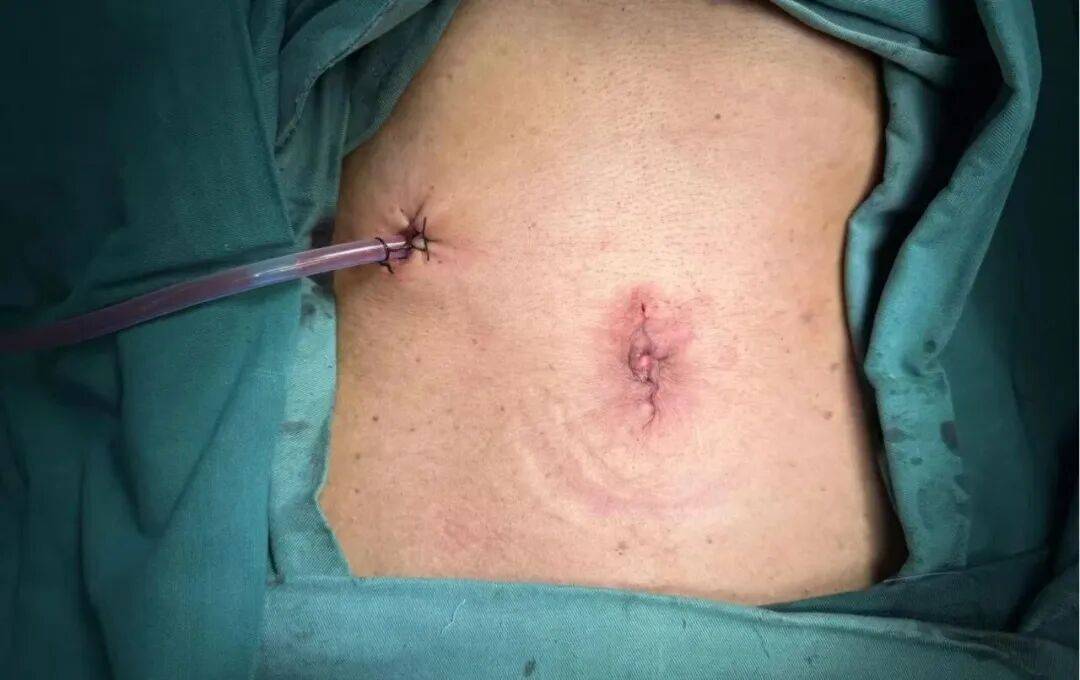

面对粘连严重、解剖结构不清的腹腔,手术团队凭借丰富的经验和精湛的技术,利用先进的单孔3D腹腔镜系统,通过腹部一个仅约3厘米的小切口,在立体、高清的放大视野下,细致地分离粘连组织,精准地完成了胃癌根治性切除与淋巴清扫。 单孔技术进一步提升了手术的微创化与美观度,而3D视野则使组织层次分明、操作如开放手术般精准,有效避免了副损伤。

尽管手术难度倍增,但在团队的密切协作下,整台手术顺利完成,出血少、创伤小。患者术后恢复迅速,次日即可下床活动,目前已顺利康复。